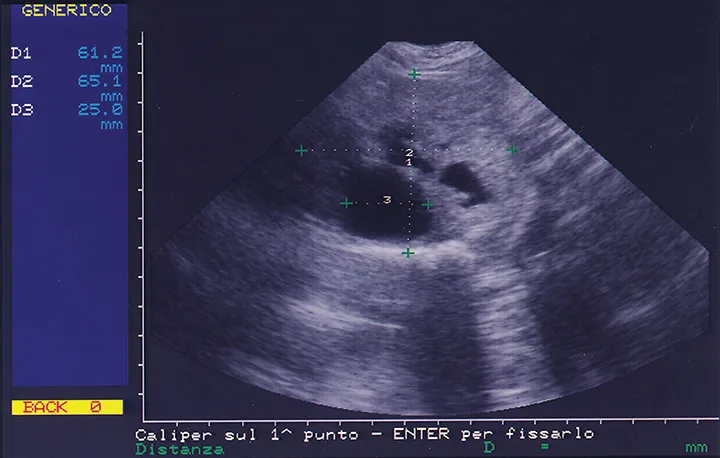

Ultrasound image of prostate with markers on screen delineating size of findings.

FIGURE 3

Ultrasonographic image of a typical aspect of canine benign prostatic hyperplasia. The prostate is increased in size (measuring 61.2 [diameter 1] × 65.1 mm [diameter 2]) and features 3 cysts, the largest of which (diameter 3) has a diameter of 2.5 cm.

The most common clinical signs of BPH are bloody penile discharge and hematuria or hematospermia.10 As the prostate enlarges, dyschezia, dysuria, poor semen quality, or infertility may be observed; this depends on the degree of prostatic fluid alterations. Increased prostatic size and presence of prostatic cysts on abdominal ultrasound are common findings (Figure 3). Urinalysis helps rule out urinary tract disease as a cause of penile discharge. Cystitis, if present, should be treated concurrently. BPH can be distinguished from prostatitis by lack of pain on transrectal prostatic palpation. Acute and chronic prostatitis will both present with leukocytes in the prostatic fluid sediment. Differentiating BPH from prostatic adenocarcinoma (PA) is more challenging, but PA is rare and is less common in intact males. A treatment course for BPH quickly eliminates clinical signs. Fine-needle aspiration or prostatic biopsies are diagnostic for PA.